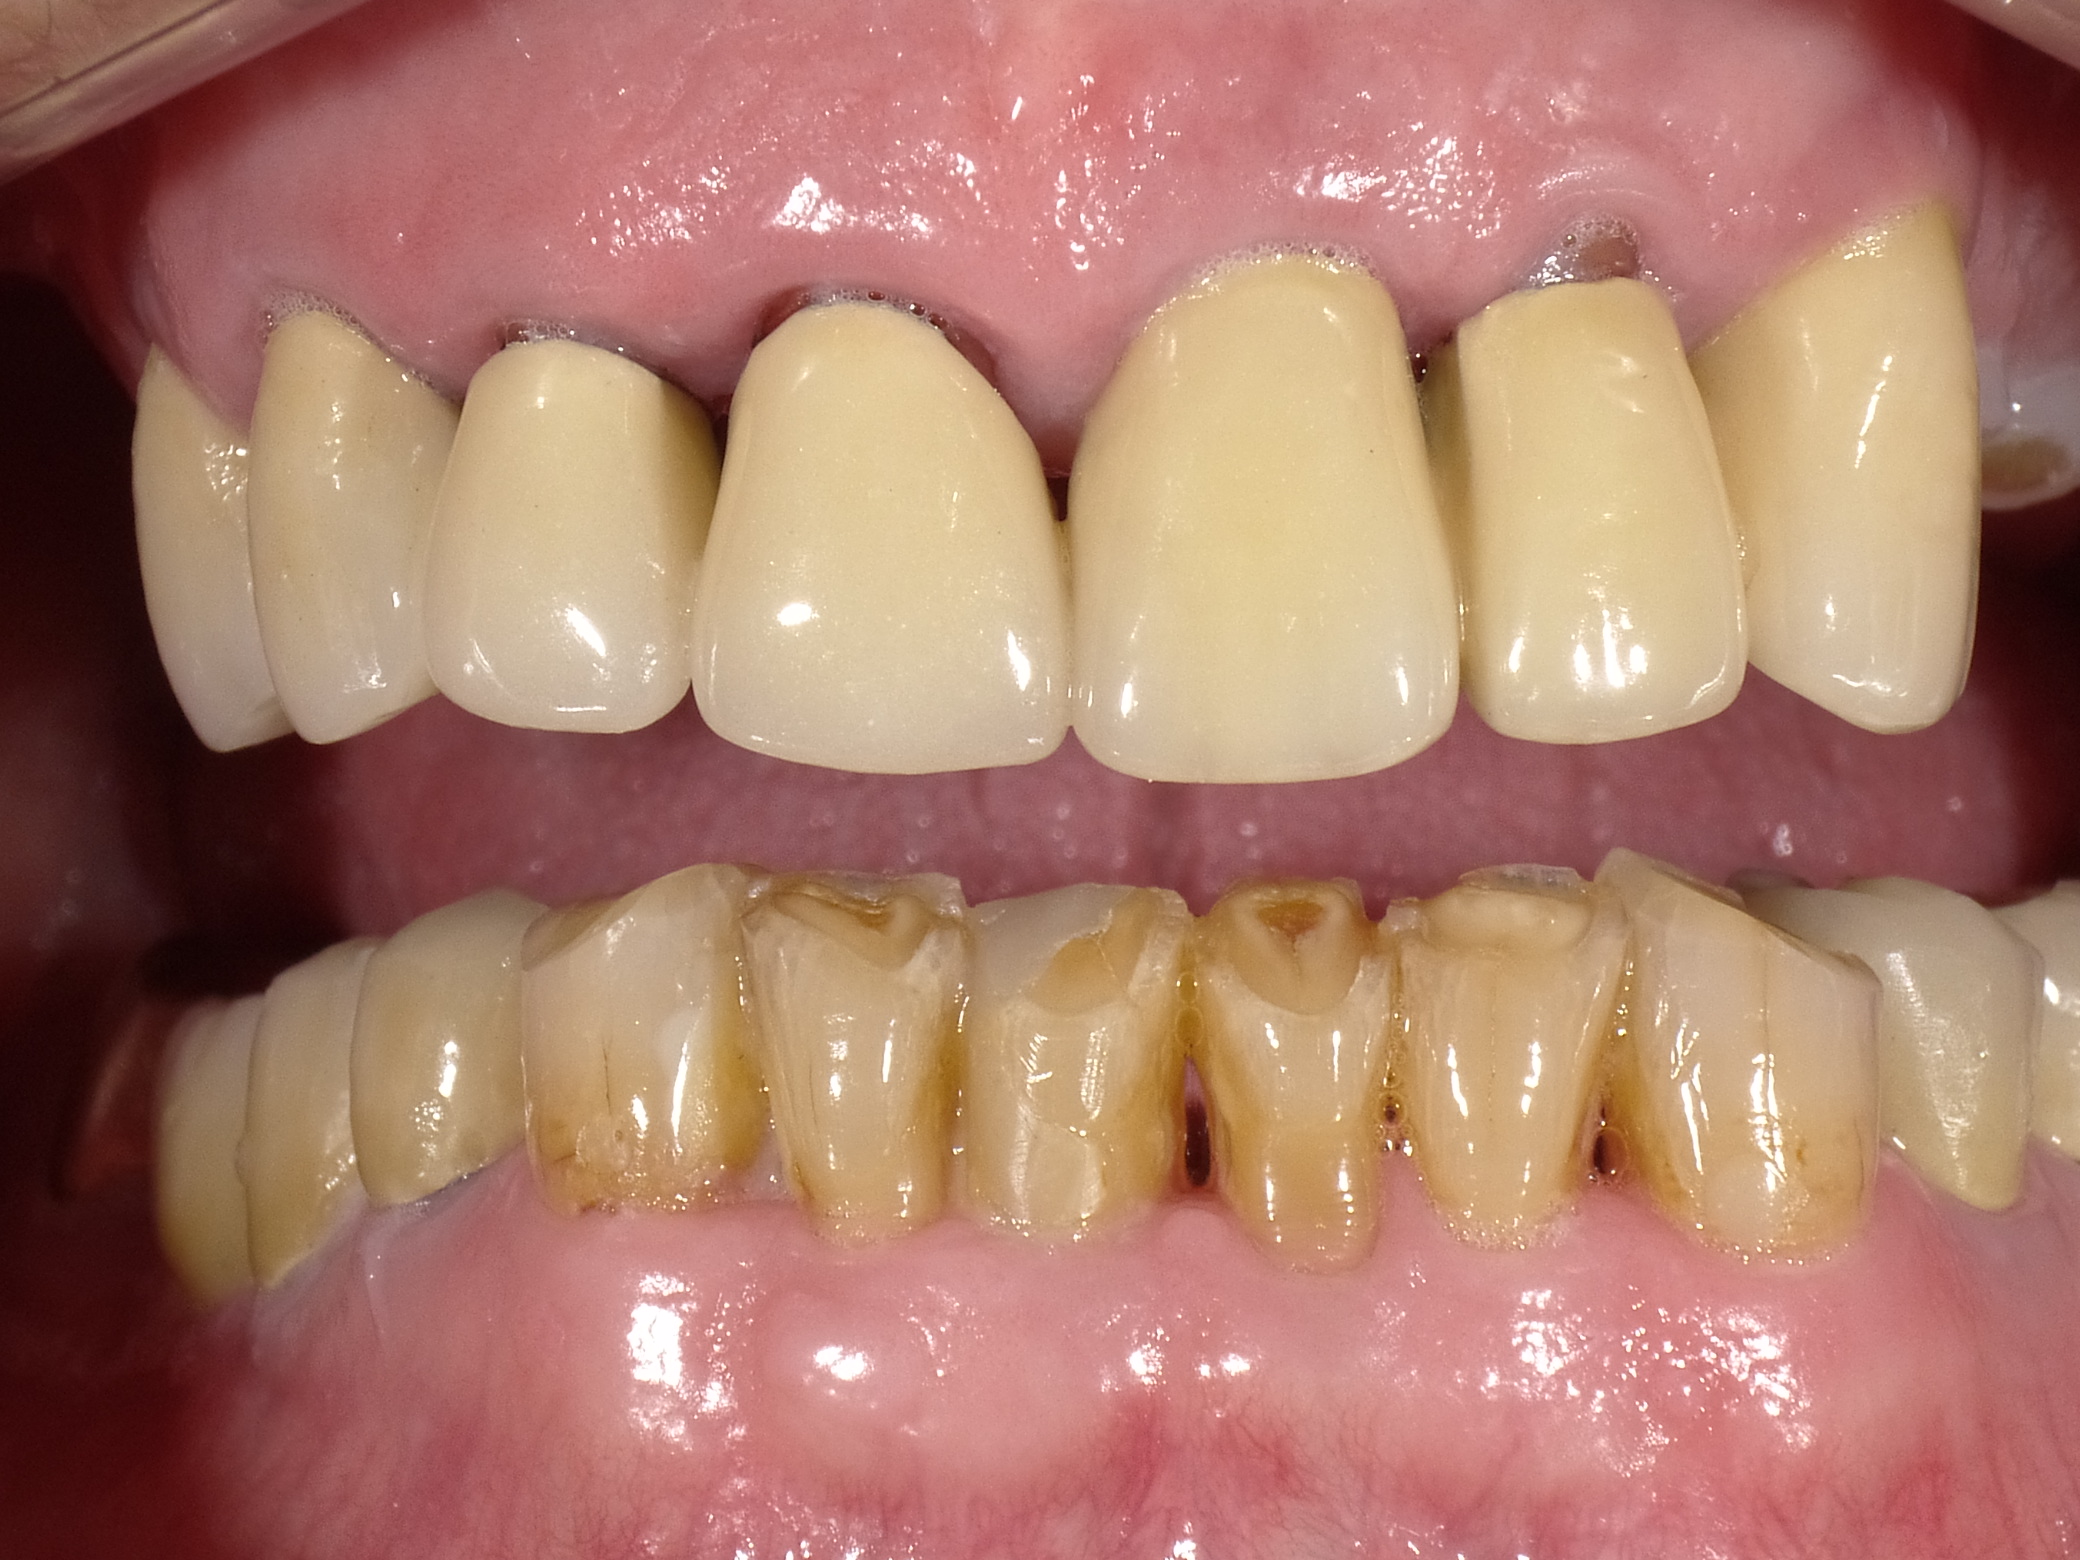

Zahnfehlstellungen und teilweise nicht mehr erhaltungsfähige Zähne durch immer wieder durchgeführte Reparaturen ohne Konzept nach Kassenrichtlinien

Vorher: Zahnfehlstellungen und teilweise nicht mehr erhaltungsfähige Zähne durch immer wieder durchgeführte Reparaturen ohne Konzept nach Kassenrichtlinien

Idealisierung im Rahmen einer Komplettbehandlung mit Vollkeramik; Ersatz der nicht erhaltungsfähigen Zähne durch Implantate

Nachher: Idealisierung im Rahmen einer Komplettbehandlung mit Vollkeramik; Ersatz der nicht erhaltungsfähigen Zähne durch Implantate